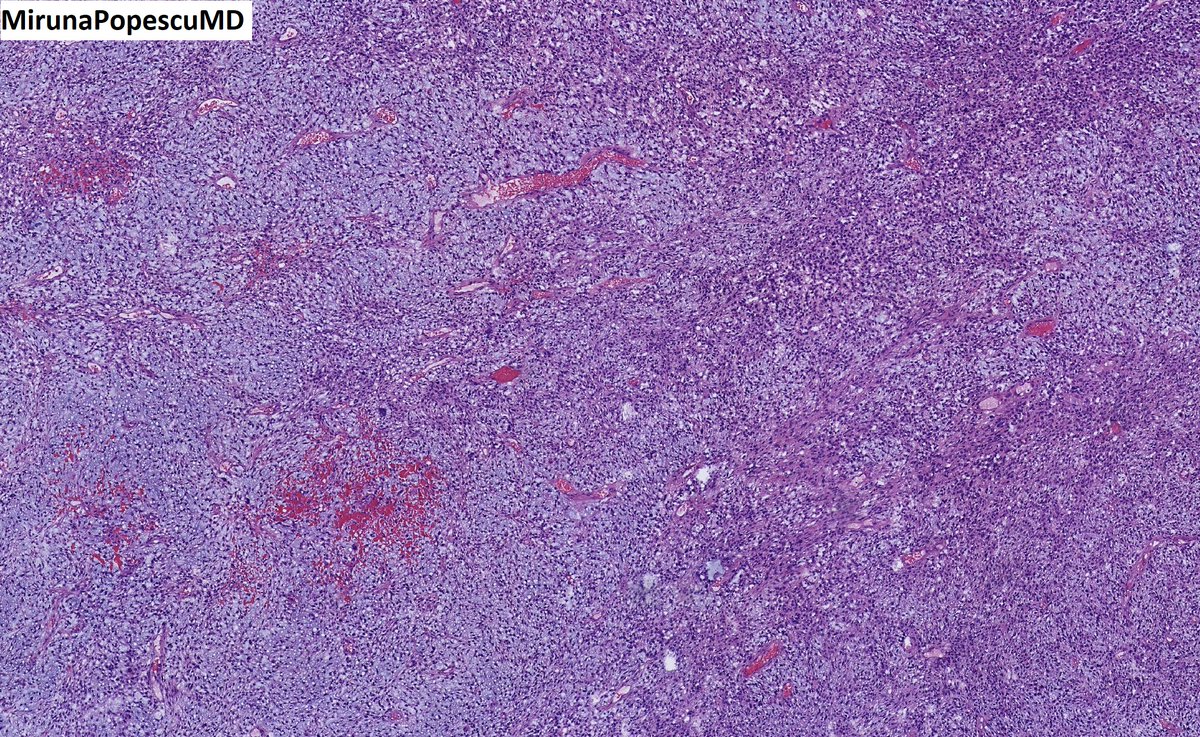

@MirunaPopescu13

Miruna Popescu, MD

3 years

❓ Let’s do a quick #BSTPath quiz ❓ 60 y/o F with a retroperitoneal mass 🔪 Follow the 🧵 👇🏽 for the answers & for a short tweetorial (1/11) #PathTwitter #pathoutpic #pathtweetorial